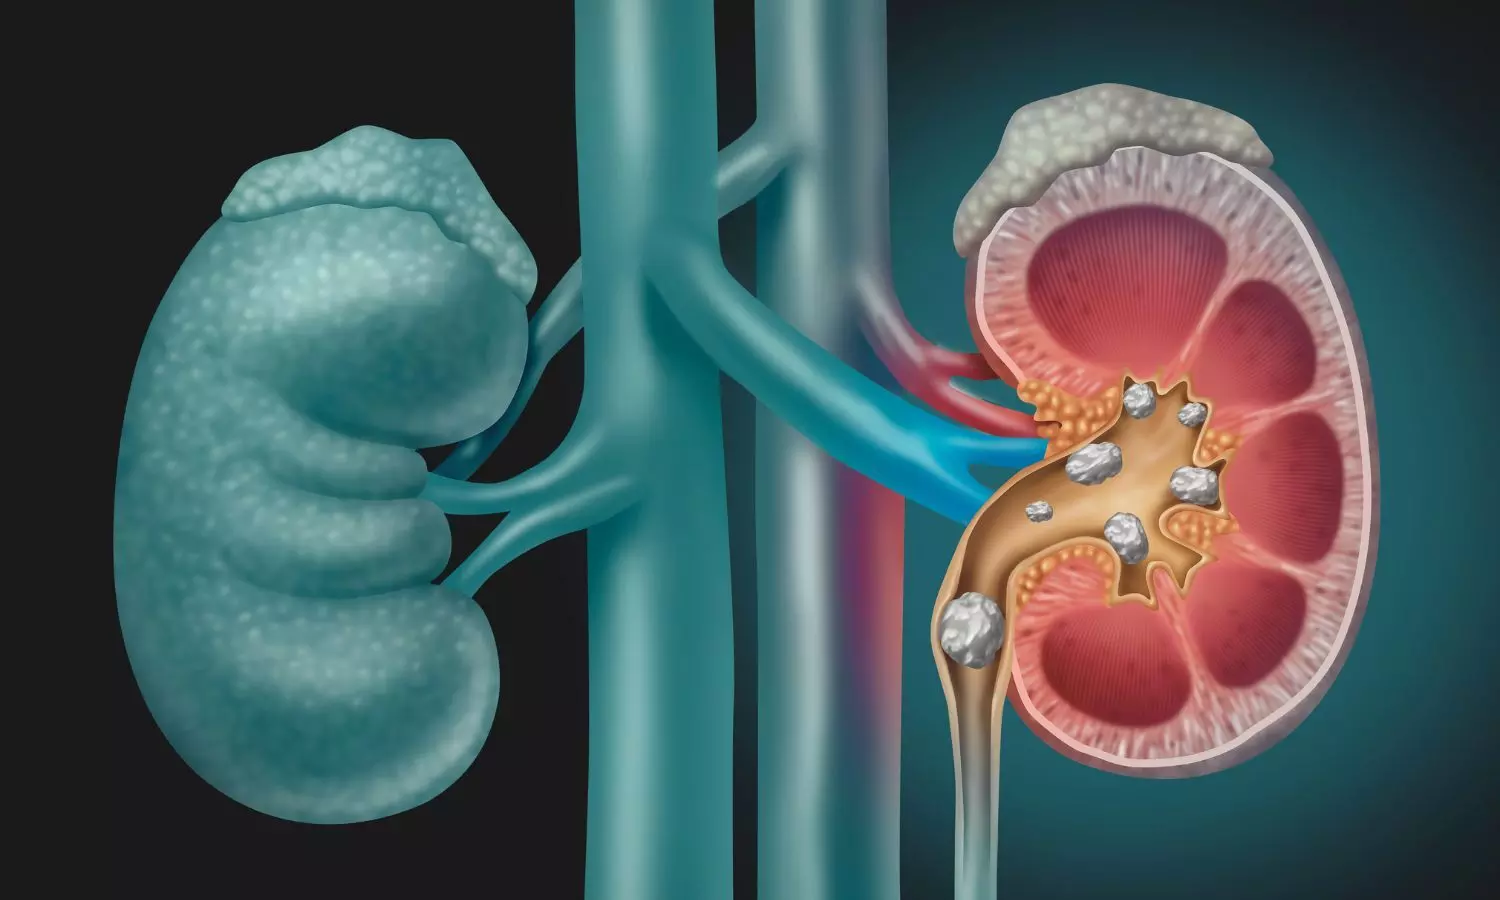

A new study published in the Canadian Urological Association Journal showed that people who acquire kidney stones have nearly double the chance of having kidney cancer as those who do not have kidney stones.

Growing research indicates that nephrolithiasis may have long-term effects on renal health, including a possible link to kidney cancer, in addition to their acute morbidity. Chronic local inflammation, recurrent epithelial damage, oxidative stress, and changes in urine composition that may encourage carcinogenesis are some of the hypothesized processes connecting kidney stones to cancer. A pro-tumorigenic renal milieu can be exacerbated by recurrent stone formation, which can also result in infections and scarring.A history of kidney stones has been linked to an increased risk of renal cell carcinoma, according to epidemiological research, albeit the strength and consistency of this correlation varies by group. Given the high prevalence of kidney stones and their potential for prevention, elucidating this link is therapeutically significant. Thus, the relationship between a history of kidney stones and the potential risk of kidney cancer was assessed in this systematic review and meta-analysis.

Overall, there is a substantial correlation between kidney stones and a higher risk of kidney cancer. These results emphasize the need of increased cancer surveillance in individuals with a history of kidney stones and point to the necessity for more investigation into common pathophysiologic processes and possible prevention measures.Source:Bhojani, N., Miller, L. E., Bhattacharyya, S., Chen, K. W., Kallidonis, P., Contreras, P. S., Somani, B. K., Gauhar, V., & Chew, B. H. (2025). Association between kidney stones and future risk of kidney cancer: A systematic review and meta-analysis: A systematic review and meta-analysis. Journal de l’Association Des Urologues Du Canada [Canadian Urological Association Journal], 20(4). https://doi.org/10.5489/cuaj.9394